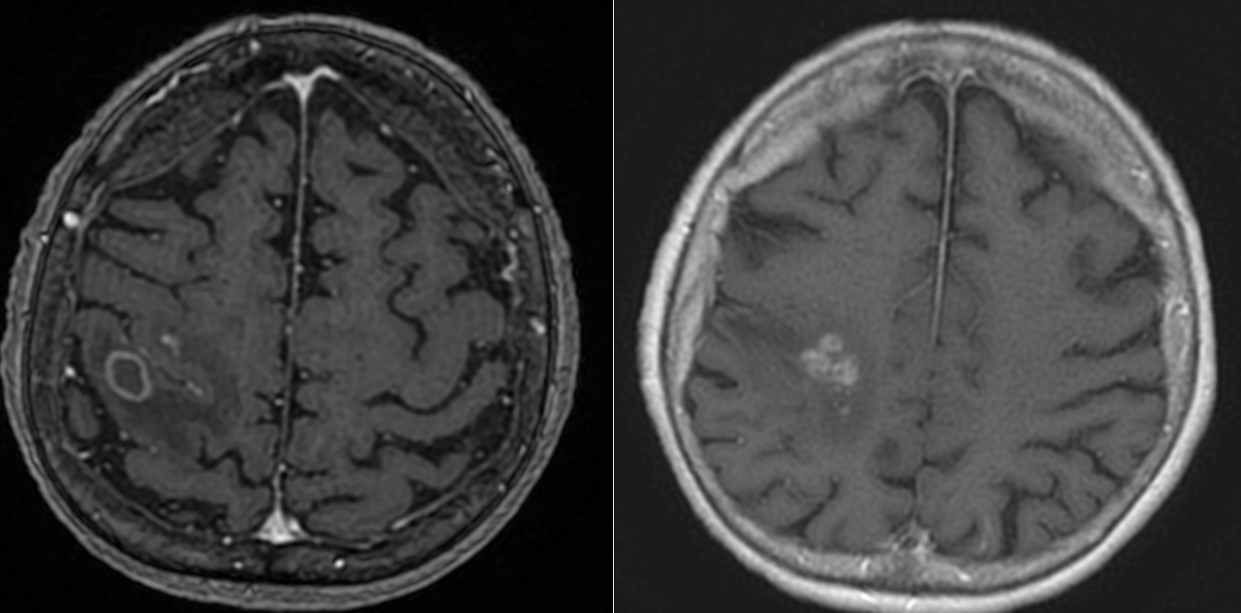

IRM cerebral cu substanță de contrast – metoda de elecție. Limfoamele sunt leziuni cu hipersemnal T2-FLAIR și hiposemnal T1, imprecis delimitate, cu contrast intens, adesea periventriculare si cu aspect caracteristic de difuzie (ADC). Poate mima glioblastomul sau metastazele cerebrale.

8. Diagnostic diferențial

- Glioblastom (datorită contrastului intens și localizării)

- Metastaze cerebrale